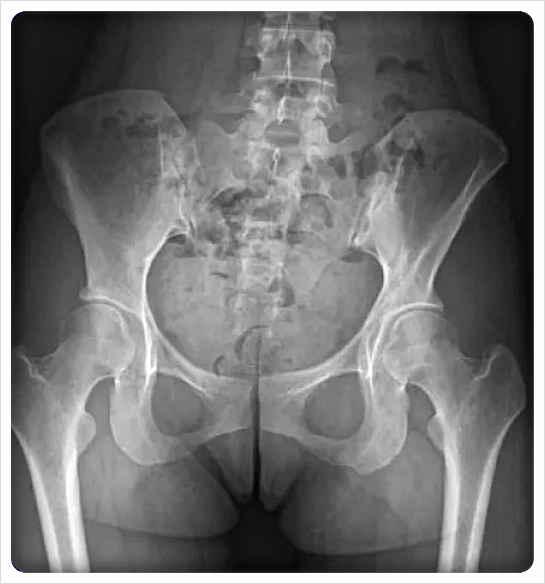

골반 벌어짐은 양쪽 골반이 바깥으로 벌어진 형태입니다.

근육 약화, 임신·출산 후 변화, 잘못된 자세 등이 복합적으로 작용할 수 있습니다.

벌어짐이 진행되면 고관절 주변 신경이 예민해져, 골반 통증뿐 아니라 다리로 이어지는 증상이 나타나기도 합니다.

그래서 “걸을 때 자꾸 삐걱거린다”는 느낌을 표현하는 분들도 있습니다.